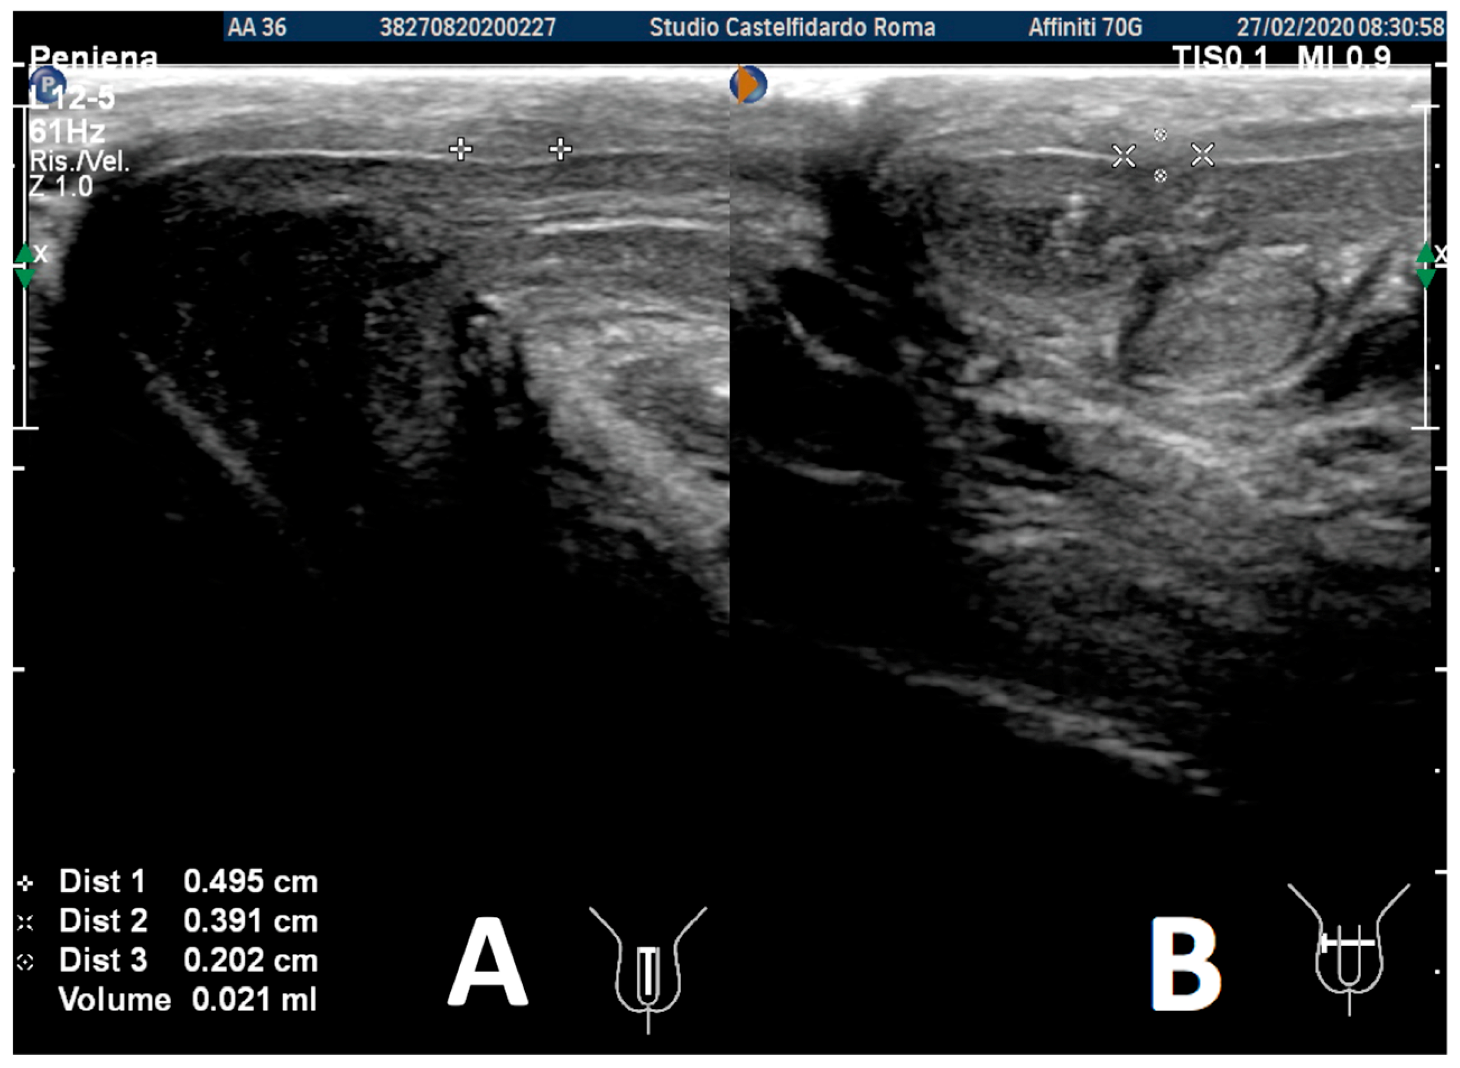

| 3 | 33 years | None | Middle third | (A) 20.6 × 15.2 × 4.42 mm volume = 724 mm3 + some small calcifications, the largest of which measured 1.9 × 4.1 mm | (A) 30-degree dorsal penile curvature | (A) score 2 | (A) score 26 | 3 years and 5 months | orally: Silymarin 400 mg + Ginkgo biloba 250 mg + Propolis 600 mg + Bilberry 160 mg + Vitamin E 800 IU/once a day, for 41 months. + topically: Propolis creme/twice a day/for 41 months. + peri-plaque penile injections: Pentoxifylline 100 mg (30 G needle) every 15 days for 6 months, and then monthly for 12 months, and then 1 injection every other month. for 12 months (total = 30 injections) |

| (B) No plaque detected | (B) None | (B) score 0 (after six months) | (B) score 27 |